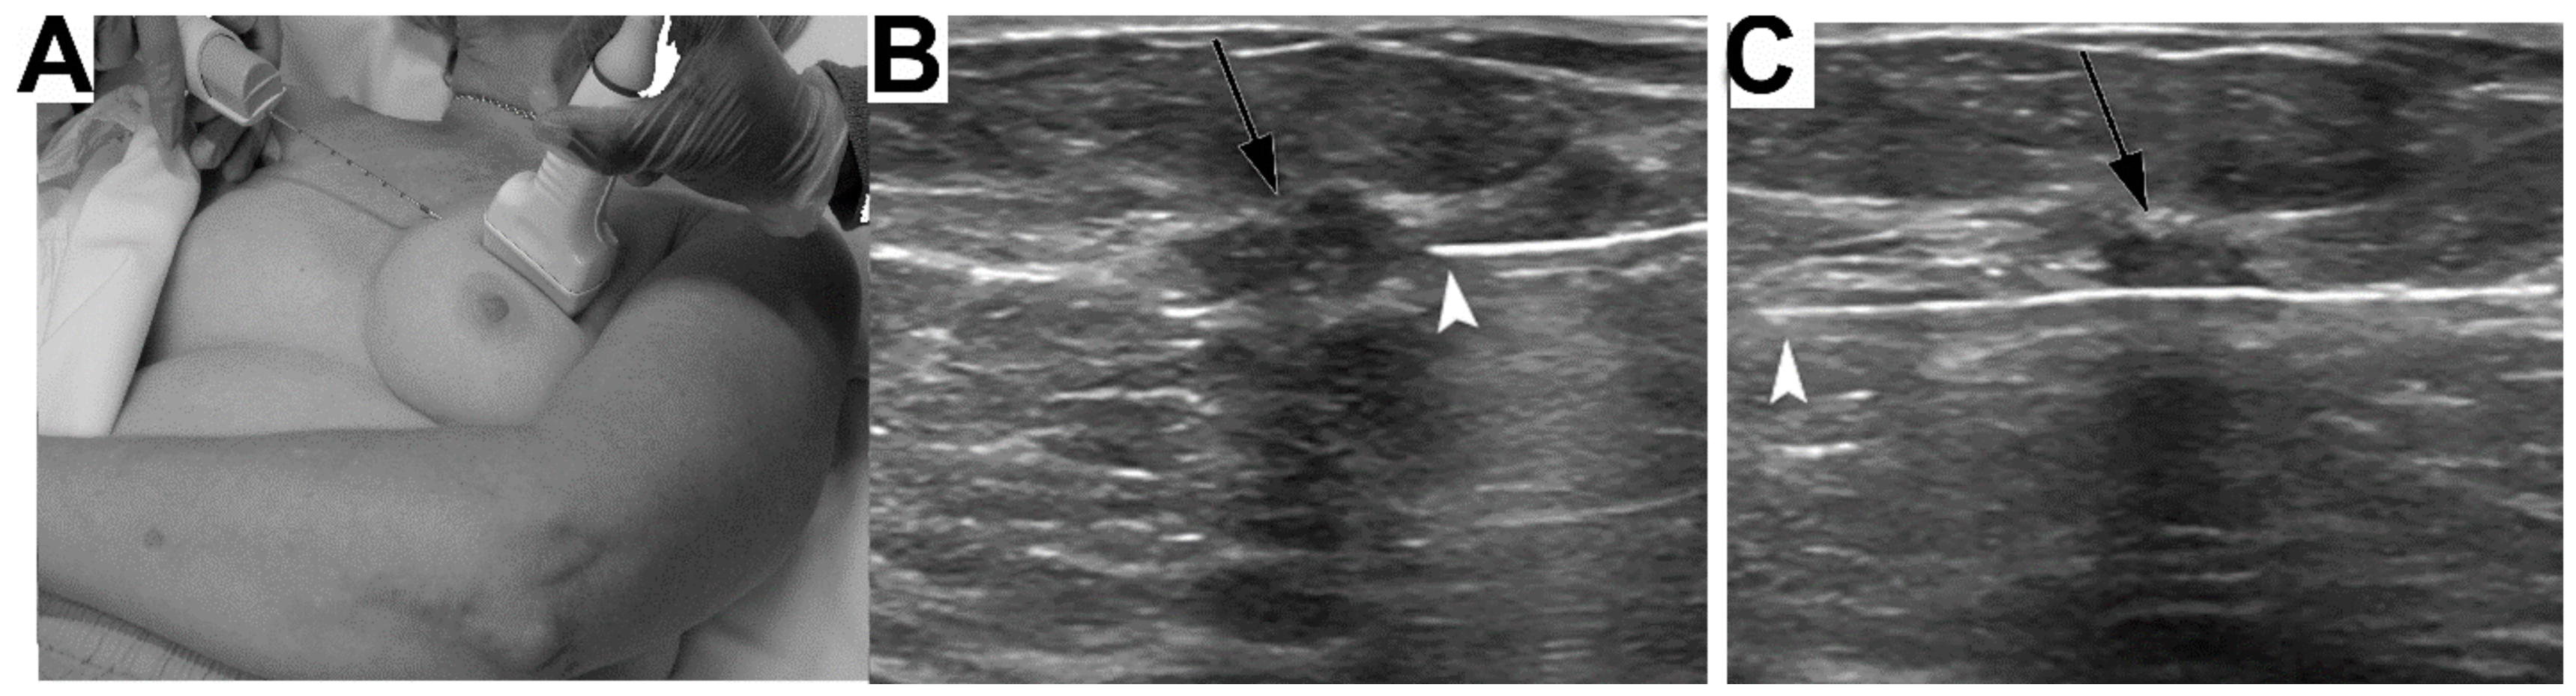

- Okello, J.; Kisembo, H.; Bugeza, S.; Galukande, M. Breast cancer detection using sonography in women with mammographically dense breasts. BMC Med. Imaging 2014, 14, 1–8. [Google Scholar] [CrossRef]

- Yuan, W.-H.; Hsu, H.-C.; Chen, Y.-Y.; Wu, C.-H. Supplemental breast cancer-screening ultrasonography in women with dense breasts: A systematic review and meta-analysis. Br. J. Cancer 2020, 123, 673–688. [Google Scholar] [CrossRef]